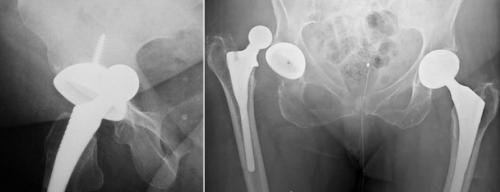

Вывих импланта.

Износ полиэтиленового вкладыша вертлужной впадины. Обратите внимание что головка находится не по центру, а смещена вверх.

Здесь изображено как поставили имплант с усиленной платформой.